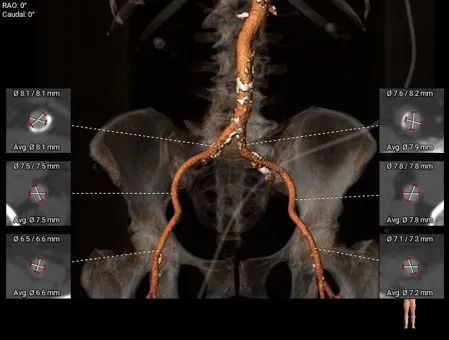

股动脉入路评估,条件相对良好

• 股-髂动脉走行适宜,内径可,穿刺点下方有钙化分布,腹主-髂总大量附壁钙化,在穿刺时准确定位穿刺点,术后需造影检查无血管并发症发生;